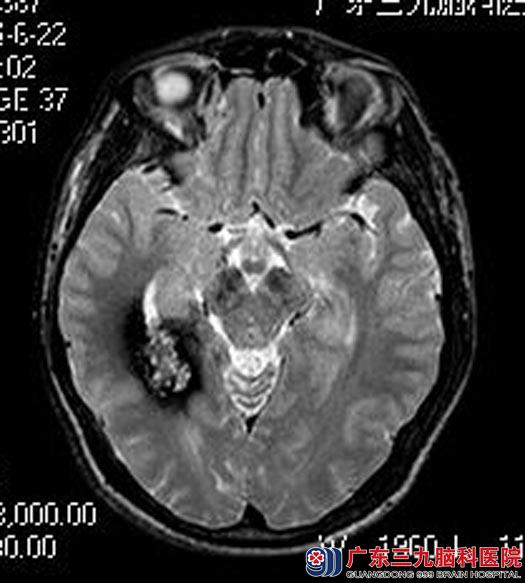

头颅MRI检查提示:右侧颞叶内后侧、右侧侧脑室后角旁异常信号影,考虑海绵状血管瘤可能性大。综合神经外科鲁明主任考虑阿华的症状是属于失神发作,口服药物治疗效果不好,建议手术切除病灶。

手术前